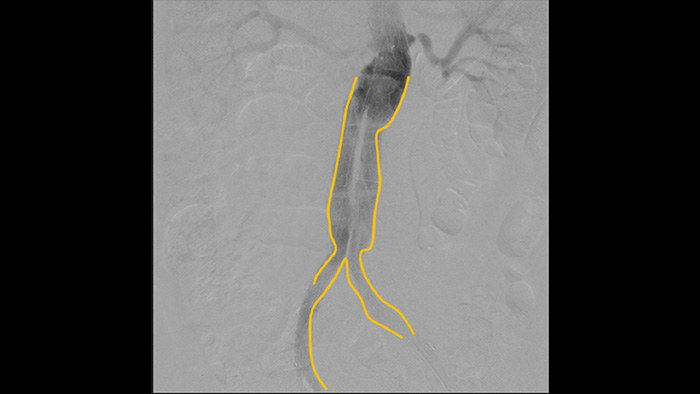

Use the Outlining tool to easily mark a bifurcation or side branches by simply drawing on the monitor of the Mobile Viewing Station with your finger or an externally connected mouse.

Digital subtraction angiography (DSA) is used in interventional vascular procedures to clearly visualise blood vessels by removing structures that can obscure vessel visibility. Roadmap fluoroscopy overlays a previously acquired subtracted contrast image on the live fluoroscopy, allowing you to track a device without reinjecting contrast.

With the Philips Zenition mobile C-arm, Dr. Vila is obtaining outstanding high-quality images that allow him to perform most vascular procedures at the low dose setting.

With the Zenition, our DSA image quality has improved greatly. We no longer see a grainy image. We just see a very clear image."

Dr. R. Vila, MD

Bellvitge University Hospital, Barcelona, Spain